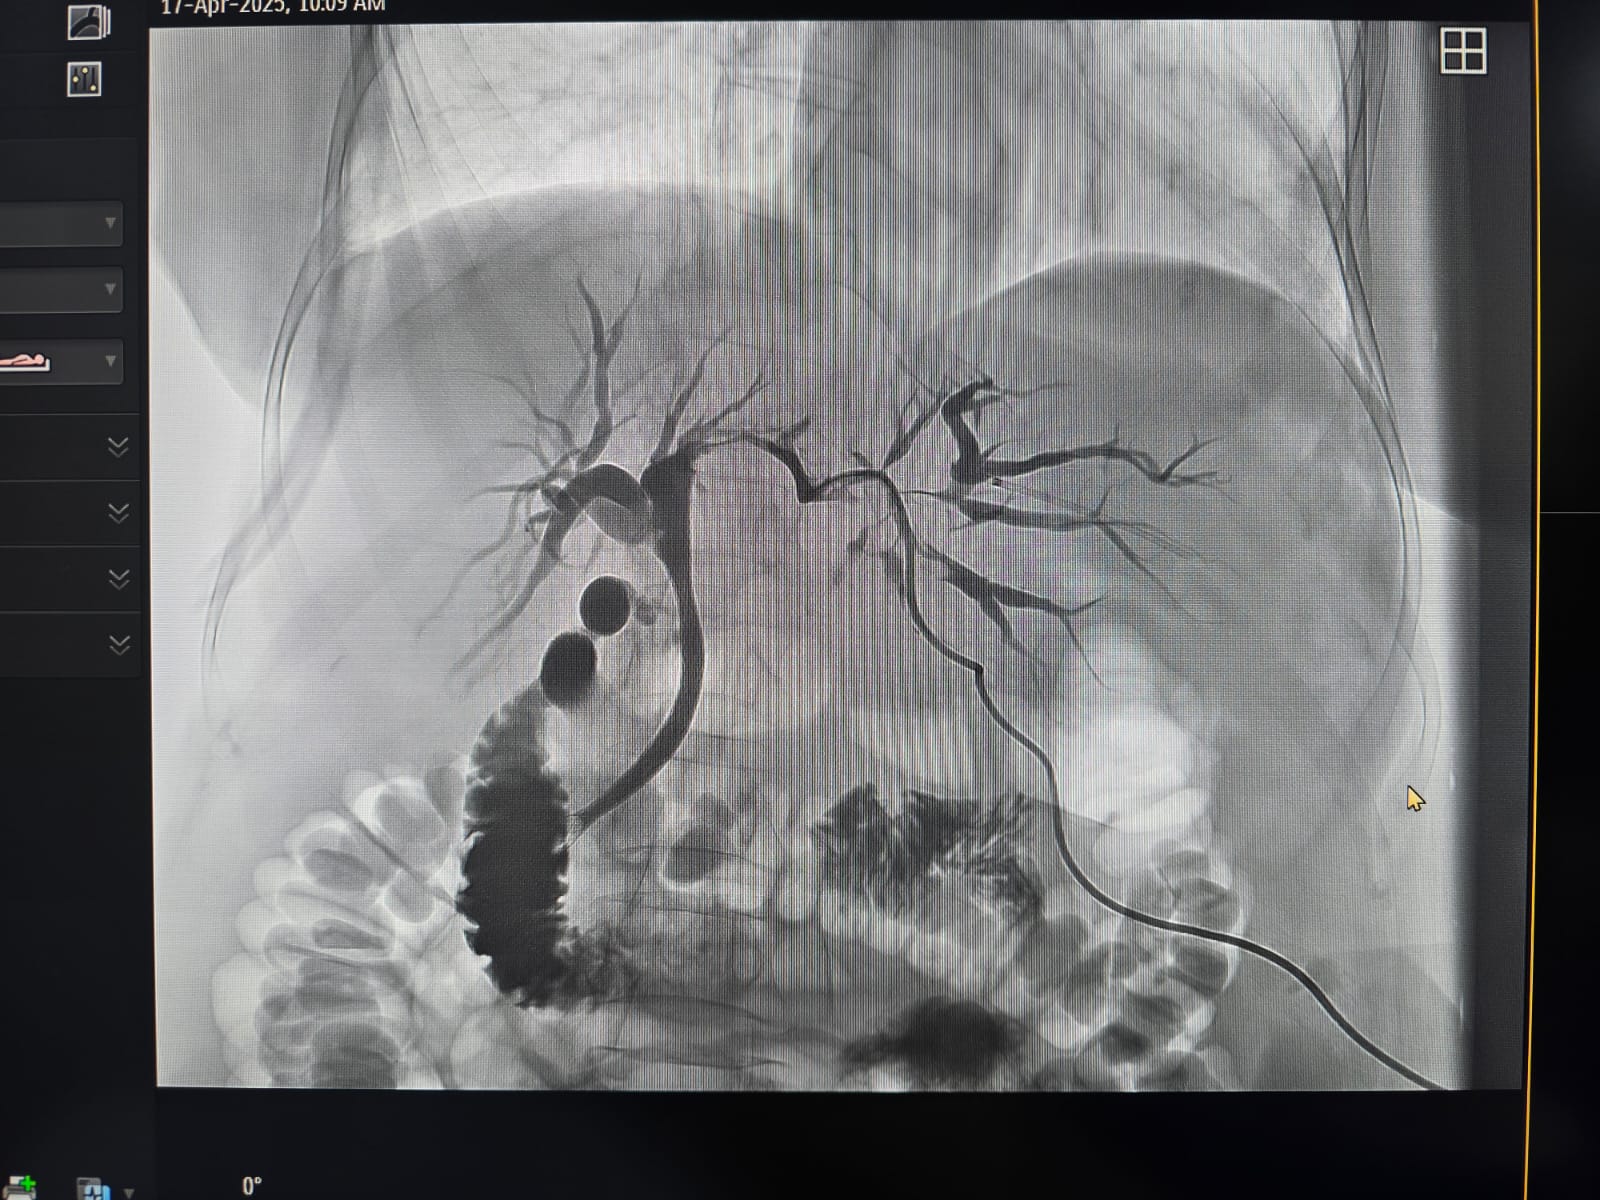

Pacienta, în vârstă de 71 de ani, cu colestază severă cauzată de o formațiune tumorală situată la nivelul hilului hepatic, a beneficiat de o abordare terapeutică multidisciplinară în două etape, în contextul unui caz considerat inoperabil chirurgical.

În prima etapă, echipa de Radiologie Intervențională a realizat cu succes un drenaj biliar percutan transhepatic. Ulterior, în a doua etapă, în colaborare cu echipa de Gastroenterologie, s-a efectuat montarea unui stent pe căile biliare extrahepatice, printr-o procedură hibridă, ghidată atât angiografic, cât și endoscopic.

„Colaborarea între specialiștii din Radiologie Intervențională, Gastroenterologie și ATI a făcut posibilă restabilirea drenajului biliar și evitarea complicațiilor majore, într-un caz cu un grad ridicat de dificultate. Această intervenție a fost posibilă datorită dotării spitalului cu angiograful utilizat în cadrul procedurii, achiziționat printr-un proiect coordonat de dr. Florin Grosu, cu sprijinul și efortul financiar al Consiliului Județean Sibiu,” mai transmit reprezentanții spitalului.